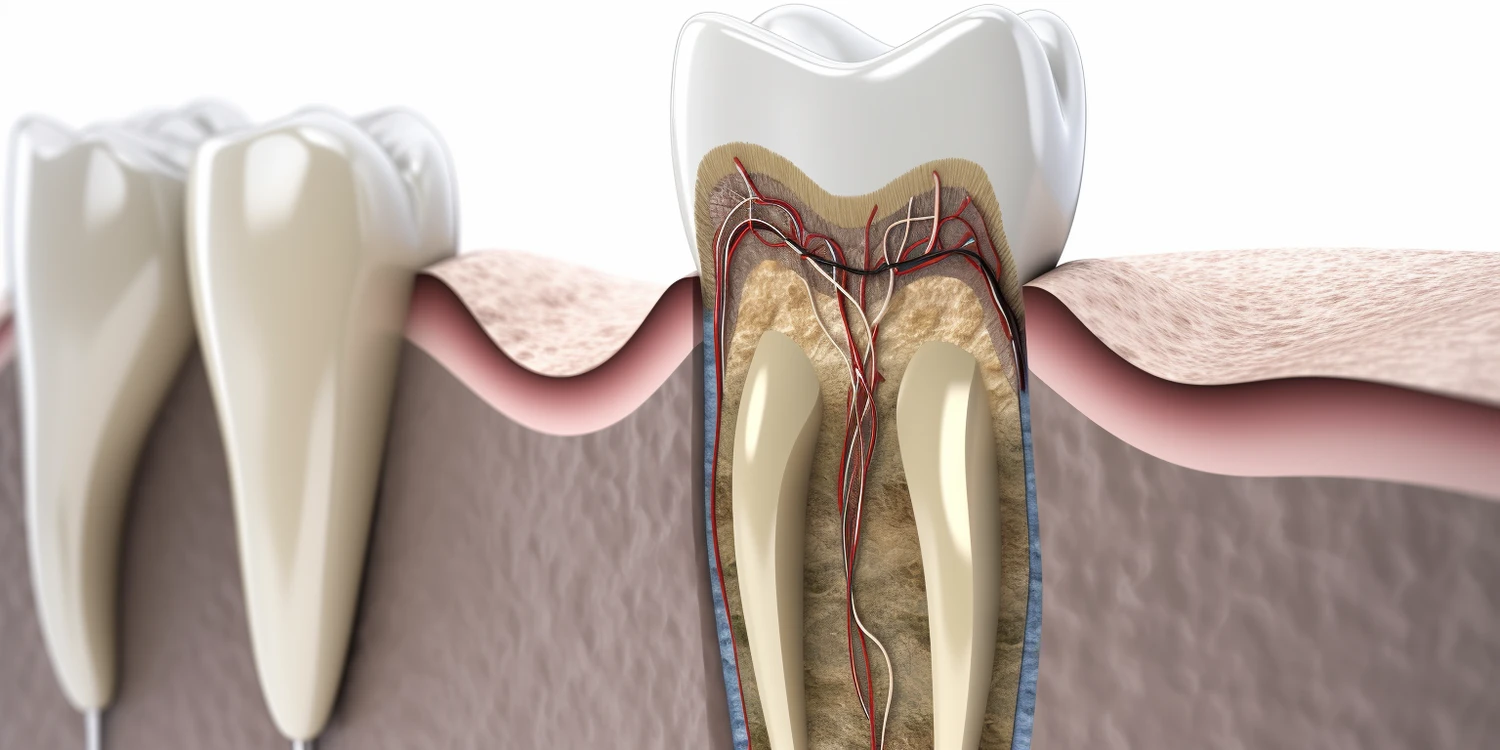

Implanty w jeden dzień Stargard

Implanty w jeden dzień w Stargardzie to innowacyjne rozwiązanie, które zyskuje coraz większą popularność wśród pacjentów poszukujących szybkiej i efektywnej metody odbudowy uzębienia. Jedną z głównych zalet tego typu zabiegu jest znaczna oszczędność czasu. Pacjenci nie muszą czekać tygodniami na zakończenie całego procesu, co jest szczególnie istotne dla osób prowadzących intensywne życie zawodowe lub rodzinne.

Ile kosztują implanty górna szczeka?

Implanty zębowe to coraz popularniejsza metoda uzupełniania braków w uzębieniu, a ich koszt może się różnić w zależności od wielu czynników. W przypadku implantów dla górnej szczęki ceny mogą być wyższe niż dla dolnej, co jest związane z bardziej skomplikowanym procesem chirurgicznym oraz większym ryzykiem powikłań. W 2023 roku średni koszt implantu zębowego w Polsce

Klinika implantologiczna Szczecin

Klinika implantologiczna w Szczecinie to miejsce, które oferuje szeroki wachlarz usług związanych z implantologią oraz stomatologią. Wśród najważniejszych usług znajdują się wszczepianie implantów zębowych, które są doskonałym rozwiązaniem dla osób borykających się z brakami w uzębieniu. Dzięki nowoczesnym technologiom oraz materiałom, jakie stosowane są w tej dziedzinie, pacjenci mogą liczyć na wysoką jakość wykonania oraz

Co należy wiedzieć przed wyborem implantu zęba?

Wybór implantu zęba to decyzja, która może znacząco wpłynąć na jakość życia pacjenta. Przed podjęciem ostatecznej decyzji warto zwrócić uwagę na kilka kluczowych aspektów. Po pierwsze, istotne jest, aby dokładnie zrozumieć, czym są implanty zębowe oraz jak przebiega ich proces zakupu i wszczepienia. Implanty to sztuczne korzenie zębów, które są wprowadzane w kość szczęki, a

Gdzie najtaniej implanty zębów?

Wybór odpowiedniego miejsca do przeprowadzenia zabiegu wszczepienia implantów zębowych jest kluczowy, zwłaszcza gdy zależy nam na kosztach. W Polsce istnieje wiele klinik stomatologicznych, które oferują różne ceny za implanty, a ich oferta często różni się w zależności od lokalizacji oraz jakości świadczonych usług. Najtańsze implanty zębów można znaleźć w mniejszych miejscowościach, gdzie koszty utrzymania są

Ile kosztuje implant zęba?

Implanty zębowe stały się popularnym rozwiązaniem dla osób, które straciły zęby i pragną przywrócić pełną funkcjonalność swojego uzębienia. Koszt implantu zęba może się znacznie różnić w zależności od wielu czynników, takich jak lokalizacja kliniki, doświadczenie stomatologa oraz użyte materiały. W Polsce ceny implantów wahają się od około 3000 do 8000 złotych za jeden implant, co

Implanty co to?

Implanty to sztuczne struktury, które są wprowadzane do organizmu w celu zastąpienia brakujących elementów, najczęściej zębów. W przypadku implantów stomatologicznych, ich głównym celem jest przywrócenie funkcji żucia oraz estetyki uśmiechu. Proces wszczepiania implantów polega na umieszczeniu tytanowego słupa w kości szczęki lub żuchwy, który następnie integruje się z tkankami kostnymi pacjenta. Tytan jest materiałem biokompatybilnym,

Implanty gdzie najlepiej opinie?

Wybór odpowiedniego miejsca do wykonania implantów zębowych jest kluczowy dla sukcesu całego zabiegu. Warto zwrócić uwagę na kilka istotnych aspektów, które mogą wpłynąć na jakość usług oraz komfort pacjenta. Przede wszystkim, należy sprawdzić doświadczenie i kwalifikacje lekarza stomatologa, który będzie przeprowadzał zabieg. Specjalistyczne kliniki stomatologiczne często zatrudniają wykwalifikowanych chirurgów szczękowych, którzy posiadają odpowiednie certyfikaty i

Ile trwa odbudowa kości pod implanty?

Odbudowa kości pod implanty stomatologiczne to proces, który może trwać różną ilość czasu w zależności od wielu czynników. Zazwyczaj czas ten wynosi od kilku miesięcy do nawet roku. Kluczowym elementem wpływającym na długość tego procesu jest stan zdrowia pacjenta oraz jakość tkanki kostnej w miejscu, gdzie planowane jest umieszczenie implantu. W przypadku pacjentów z niedoborem

Ile kosztują zęby implanty?

Ceny implantów zębowych różnią się znacznie w zależności od kraju, w którym są wykonywane. W krajach zachodnich, takich jak Stany Zjednoczone czy Wielka Brytania, koszty mogą być znacznie wyższe niż w krajach Europy Wschodniej. Na przykład w USA cena jednego implantu może wynosić od 3000 do 4500 dolarów, co obejmuje zarówno sam implant, jak i

Ile kosztują implanty wszystkich zębów?

Implanty zębowe stały się popularnym rozwiązaniem dla osób, które straciły zęby i pragną przywrócić pełną funkcjonalność oraz estetykę uśmiechu. Koszt implantów wszystkich zębów w Polsce może się znacznie różnić w zależności od wielu czynników, takich jak lokalizacja kliniki, doświadczenie lekarza oraz użyte materiały. Średni koszt jednego implantu w Polsce wynosi od 3000 do 6000 złotych,

Ile kosztuje implanty zębów?

Koszt implantów zębów może znacznie różnić się w zależności od kraju, w którym są one wykonywane. W krajach zachodnich, takich jak Stany Zjednoczone czy Wielka Brytania, ceny mogą być znacznie wyższe niż w krajach Europy Środkowo-Wschodniej. Na przykład w USA koszt jednego implantu zęba może wynosić od 3000 do 4500 dolarów, co obejmuje zarówno sam

Czy implanty zębów trzeba wymieniać?

Implanty zębów to coraz bardziej popularna metoda uzupełniania braków w uzębieniu, jednak wiele osób zastanawia się, czy wymagają one wymiany po pewnym czasie. Warto zaznaczyć, że implanty zębowe są zaprojektowane tak, aby były trwałe i funkcjonalne przez wiele lat, a nawet przez całe życie pacjenta. Kluczowym czynnikiem wpływającym na ich długowieczność jest jakość materiałów, z

Jak długo wytrzymują implanty zębów?

Implanty zębowe to jedna z najskuteczniejszych metod uzupełniania braków w uzębieniu. Ich trwałość zależy od wielu czynników, w tym od jakości materiałów użytych do ich produkcji, umiejętności chirurga oraz dbałości pacjenta o higienę jamy ustnej. W praktyce implanty mogą wytrzymać od 10 do 15 lat, a niektóre przypadki pokazują, że przy odpowiedniej pielęgnacji mogą funkcjonować

Dentysta Szczecin implanty

Implanty dentystyczne to jedno z najnowocześniejszych rozwiązań w stomatologii, które cieszy się rosnącą popularnością w Szczecinie. Dzięki nim pacjenci mogą odzyskać pełną funkcjonalność zębów oraz estetyczny uśmiech. Jedną z głównych zalet implantów jest ich trwałość. W przeciwieństwie do tradycyjnych protez, które mogą wymagać częstej wymiany, implanty są zaprojektowane tak, aby służyły przez wiele lat, a

Implanty Lublin cena

Ceny implantów w Lublinie mogą się znacznie różnić w zależności od wielu czynników, które warto rozważyć przed podjęciem decyzji o leczeniu. Przede wszystkim, cena implantów dentystycznych jest uzależniona od rodzaju użytych materiałów oraz technologii, które są stosowane w danym gabinecie stomatologicznym. W Lublinie można znaleźć zarówno tańsze oferty, jak i te z wyższej półki, co

Implanty Szczecin cena

Ceny implantów w Szczecinie mogą się znacznie różnić w zależności od wielu czynników. Przede wszystkim, kluczowym elementem jest wybór kliniki stomatologicznej, która oferuje usługi implantologiczne. Renomowane placówki z doświadczonymi specjalistami często mają wyższe ceny, ale mogą również zapewniać lepszą jakość usług oraz nowoczesny sprzęt. Kolejnym czynnikiem wpływającym na koszt jest rodzaj implantu. Na rynku dostępne